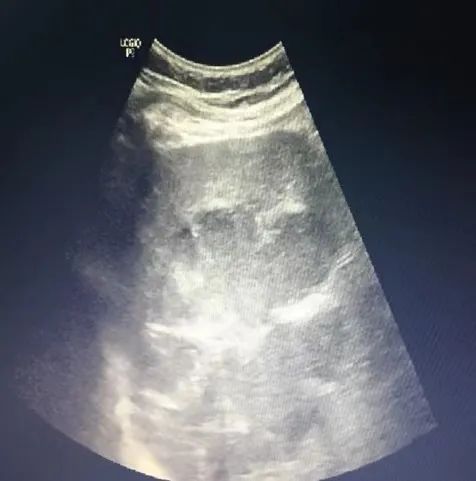

腹部彩超示: 1.肝脾大,肝内低回声,考虑肝囊肿,进一步检查;2.胆囊结石;3.左肾囊肿;

术前彩超示:肝右后叶可探及大小12.2×8.7cm的低回声包块,其内可见分隔光带,术中引流出约100ml浅咖啡色粘稠脓液,术后患者未再有发热,术后3天复查肝功能呈持续好转趋势,CRP、血白细胞等指标明显下降。